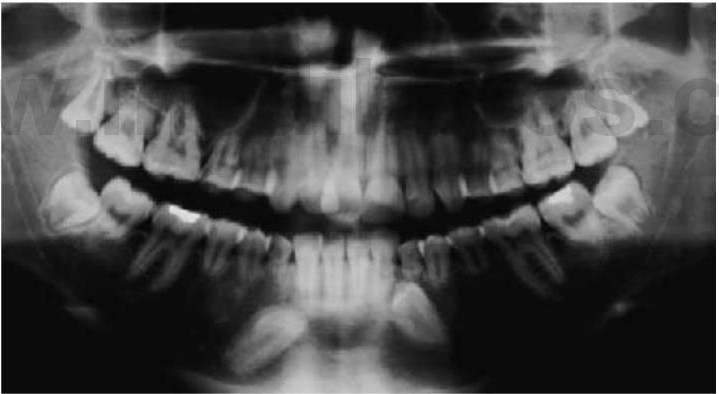

Hipodoncia, oligodoncia y anodoncia son los términos que designan los diferentes grados de progresión de la ausencia de dientes, si bien el término hipodoncia es el más utilizado debido a que se refiere a un número indeterminado de dientes ausentes (fig. 9.1 A). La oligodoncia designa la ausencia de seis dientes o más, y la anodoncia la ausencia completa de dientes. Todos estos casos se producen debido a un fallo en el desarrollo. El término «dientes ausentes congénitamente» no puede aplicarse a la dentición permanente, ya que estos dientes comienzan su desarrollo después del nacimiento, y tampoco a la dentición temporal ya que esa ausencia dental no puede determinarse de forma clínica en el momento de nacer; asimismo, el término «anodoncia parcial» carece de sentido. Sucede con frecuencia que los grados de hipodoncia aparezcan de manera esporádica o bien tengan un componente hereditario. Cuando a un individuo le faltan muchos dientes se debe estudiar a otros miembros de la familia afectados.

Los dientes que faltan con mayor frecuencia son los últimos de cada serie, es decir, el incisivo lateral, el segundo premolar y el tercer molar, y es realmente infrecuente la falta de los incisivos centrales, los caninos o los primeros molares permanentes. En el plano clínico, tiene mayor importancia el tipo de dientes ausentes que su número. La presencia de un diente rudimentario o cónico puede estar asociada a la ausencia del mismo diente del lado opuesto de la arcada. Un ejemplo frecuente es la microdoncia del incisivo lateral, que también puede estar ausente en descendientes del paciente afectado. Las ausencias de dientes son una manifestación de muchos síndromes de cabeza y cuello.

- Varios dientes ausentes (fig. 9.1 B).